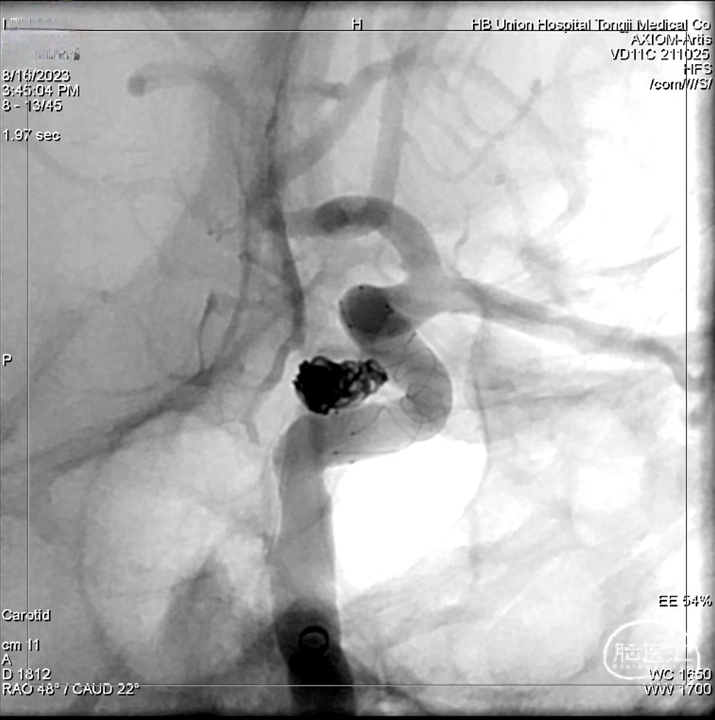

● 术前3D及工作角度,示瘤体形态不规则。

● 支架半释放状态逐步填入弹簧圈,至动脉瘤不显影,后彻底释放支架;

● 造影示载瘤动脉通畅,支架贴壁良好。